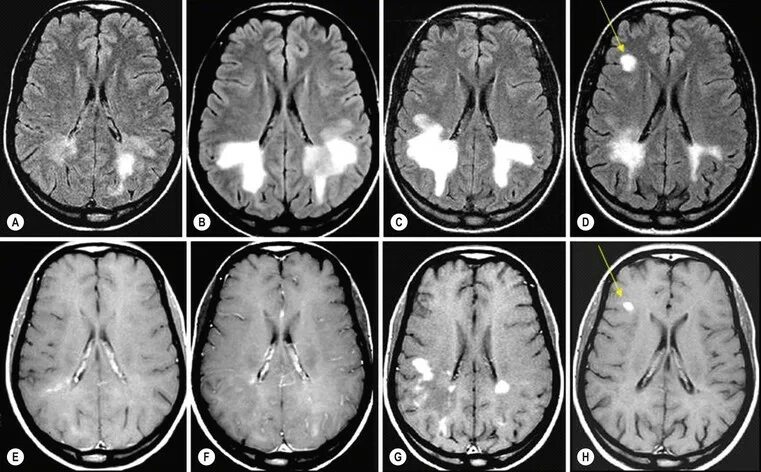

Диффузная церебральная атрофия степени